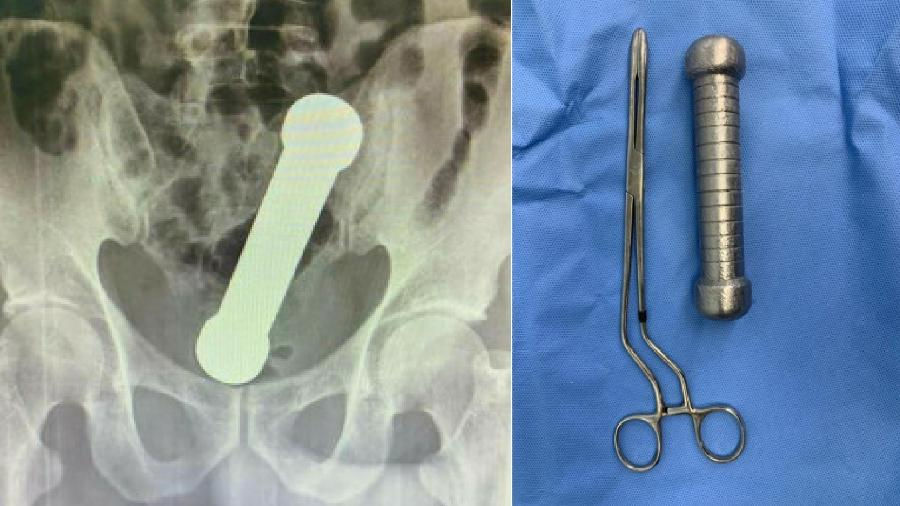

Os profissionais envolvidos no atendimento destacaram a complexidade do caso. A retirada de objetos retais é uma ocorrência conhecida na medicina de emergência, porém o peso e o formato específico do halter representavam um risco significativo, especialmente para perfuração intestinal e hemorragias internas. O artigo detalha o uso de técnicas específicas de sedação, manobras abdominais e instrumentos cirúrgicos minimamente invasivos para realizar a remoção sem a necessidade de cirurgia aberta.

Felizmente, após cerca de uma hora de procedimento, o halter foi removido com sucesso. O paciente permaneceu em observação por 48 horas e recebeu alta hospitalar sem complicações graves. O relatório enfatiza a importância de manter uma abordagem não julgadora e técnica ao lidar com situações semelhantes, ressaltando o papel da empatia e da ética médica no atendimento a casos sensíveis.